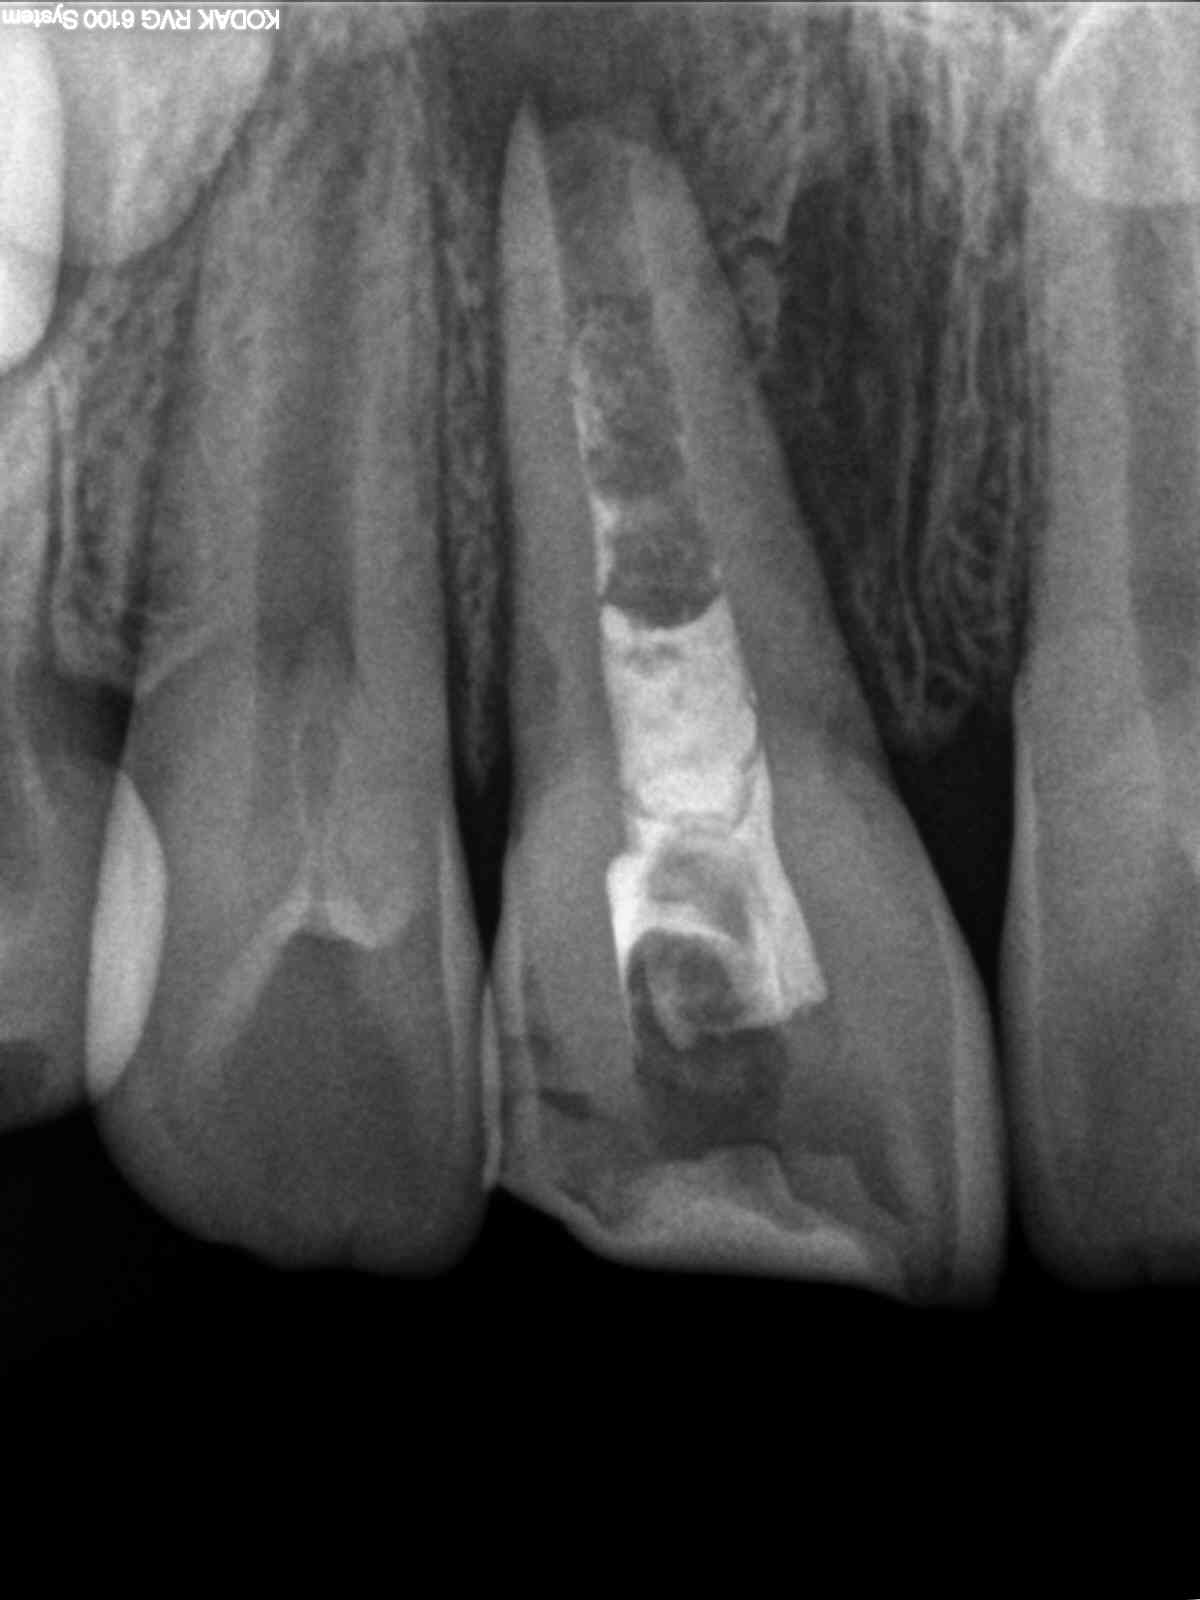

Späte Apexogenese